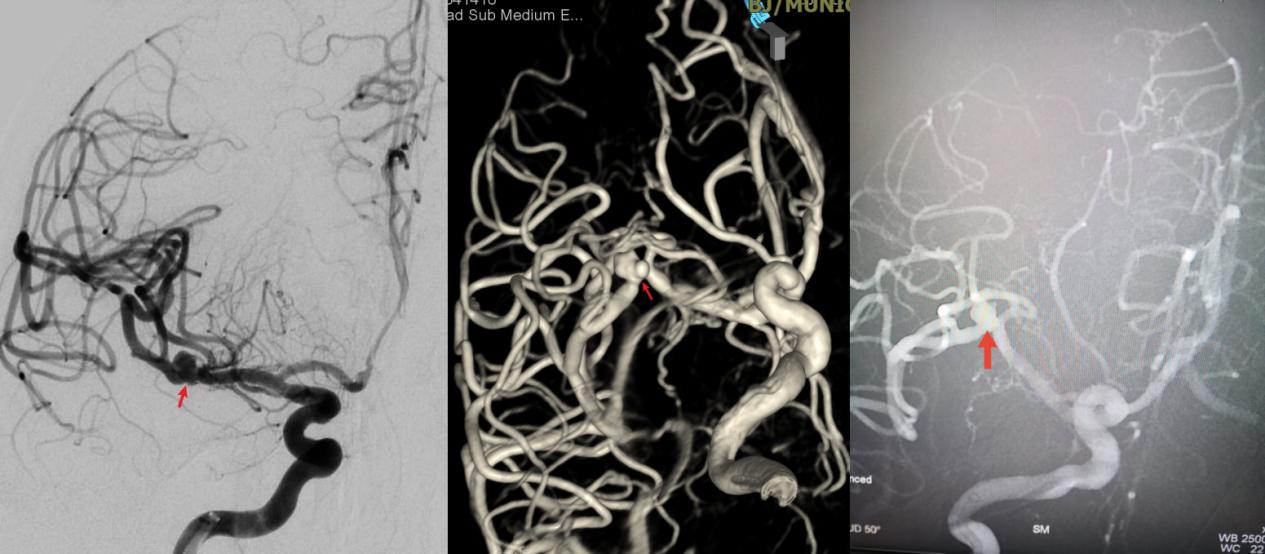

病例一为77岁女性患者,既往高血压病史。因“突发剧烈头痛伴恶心2天”前来清华大学附属垂杨柳医院急诊科就诊。头颅CT检查提示蛛网膜下腔出血,头颈动脉CTA提示右侧大脑中动脉M1段分叉处宽颈动脉瘤。神经外科脑血管病介入团队急诊为患者实施了全脑血管造影术(DSA),造影显示动脉瘤不规则,可见子囊,宽颈,主要累及下干。团队采取了支架辅助弹簧圈栓塞术,患者颅内“不定时炸弹”被成功拆除。动脉瘤达到致密栓塞,载瘤动脉通畅。住院半个月后顺利出院,无神经功能障碍。

▲术前DSA显示宽颈动脉瘤,有子囊,主要累及下干

▲术后DSA显示动脉瘤致密栓塞,载瘤动脉通畅